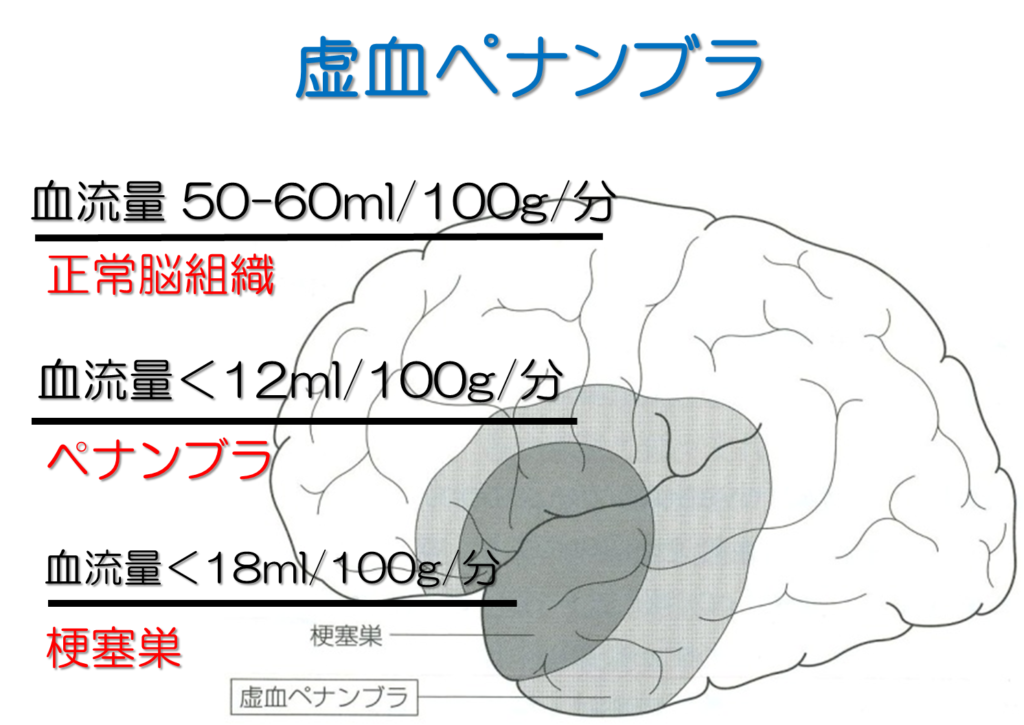

アテローム血栓症が注目されています

脳梗塞の初期症状を確認して命を守る

医師監修 作成 脳梗塞と脳卒中の違いをご存知ですか Medley メドレー

脳梗塞の種類 分類 まとめ 心原性 アテローム血栓性 ラクナ梗塞